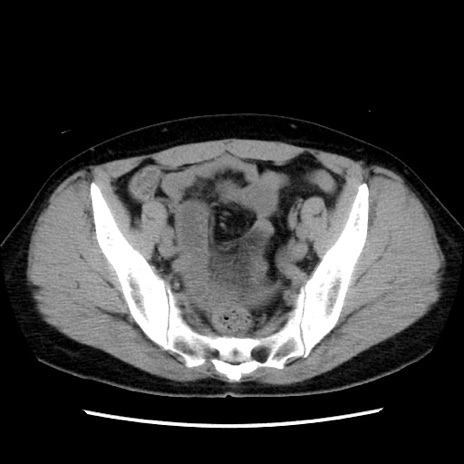

矢状断像

【症例】 50歳代女性

【主訴】 腹痛

【現病歴】前日生レバーを食べた。今朝に排便あり。 昼前に突然発症の腹痛を生じ、当院救急外来を受診した。

【既往歴】 子宮筋腫にてで子宮全摘後

【身体所見】 意識清明、腹部:平坦、軟、下腹部やや左を中心に圧痛・反跳痛あり、筋性防御あり

【データ】WBC 7800、CRP 0.07